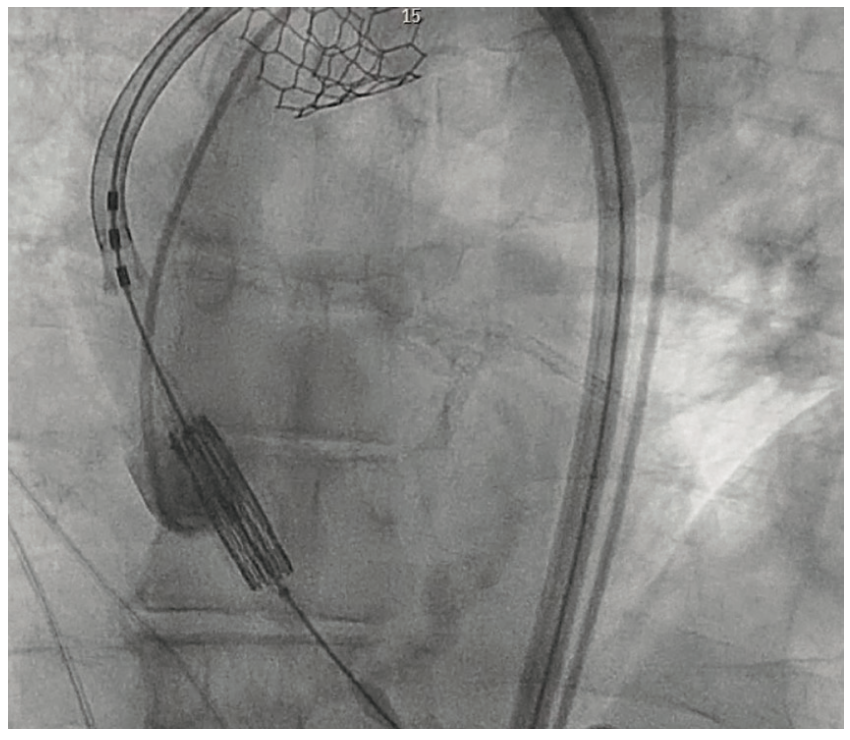

During the TAVR procedure, a Sapien 3 26 mm valve was loaded over a Safari wire (Boston Scientific) and advanced into the aortic annulus under fluoroscopy, with good planar angle positioning confirmed using contrast injection. After valve placement, rapid ventricular pacing was performed and the valve was deployed. However, immediately following deployment, the valve embolized into the ascending aorta. The valve was carefully pulled distally and secured just proximal to the origin of the right brachiocephalic artery. It was dilated with an extra 4 mL volume with two inflations performed. To confirm the patency of the right subclavian artery and the right brachiocephalic artery, access was subsequently obtained in the right radial artery, and no difference in the arterial pressure was noted as the catheter was advanced from the right radial artery into the aortic root. A second Sapien 3 26 mm valve was then loaded over the Safari wire and was similarly advanced into the aortic annulus under fluoroscopy, with good coplanar angle positioning confirmation via contrast injection. After rapid ventricular pacing, the second valve was deployed without issue. A post procedure aortogram confirmed good valve positioning, the absence of significant paravalvular leak, and patency of the left coronary artery. A limited echocardiogram also confirmed good valve positioning, the absence of paravalvular leak, and the absence of pericardial effusion. The patient tolerated the procedure well and left the cardiac catheterization laboratory in a stable condition. After chest x-ray confirmed stable positioning of the embolized valve in the ascending aorta, the patient was discharged on postoperative day one with a scheduled follow-up visit in three weeks.